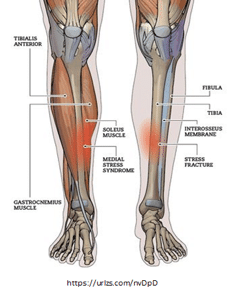

Shin splint pain can be muscular related pain or it can be bone related which is also called medial tibial stress syndrome. What happens is that the impact from landing on your feet with running can cause your bone and muscle tissue to break down and start to swell and become inflamed. If you continue to run when your shins are hurting, over time this will cause further break down and this is when people may develop a stress reaction or fracture. Bone injuries take longer to heal, so if you are having shin pain start physical therapy right away!

Overtraining/ overuse injuries like shin splints occur when you increase your intensity, duration or frequency of impact exercise such as running too quickly. It is important to have a good training program that is gradual. There are some other causes for shin splints and your physical therapist can help you identify what these are. A few of these are listed below:

Causes:

- Running mechanics

- Foot posture/shoe wear

- Ankle/Hip weakness

- Training errors

- Increase intensity/ frequency

- Hill training early in season/ in training

- Running on cement or hard surfaces

- Bone Mineral Density

- Nutrition